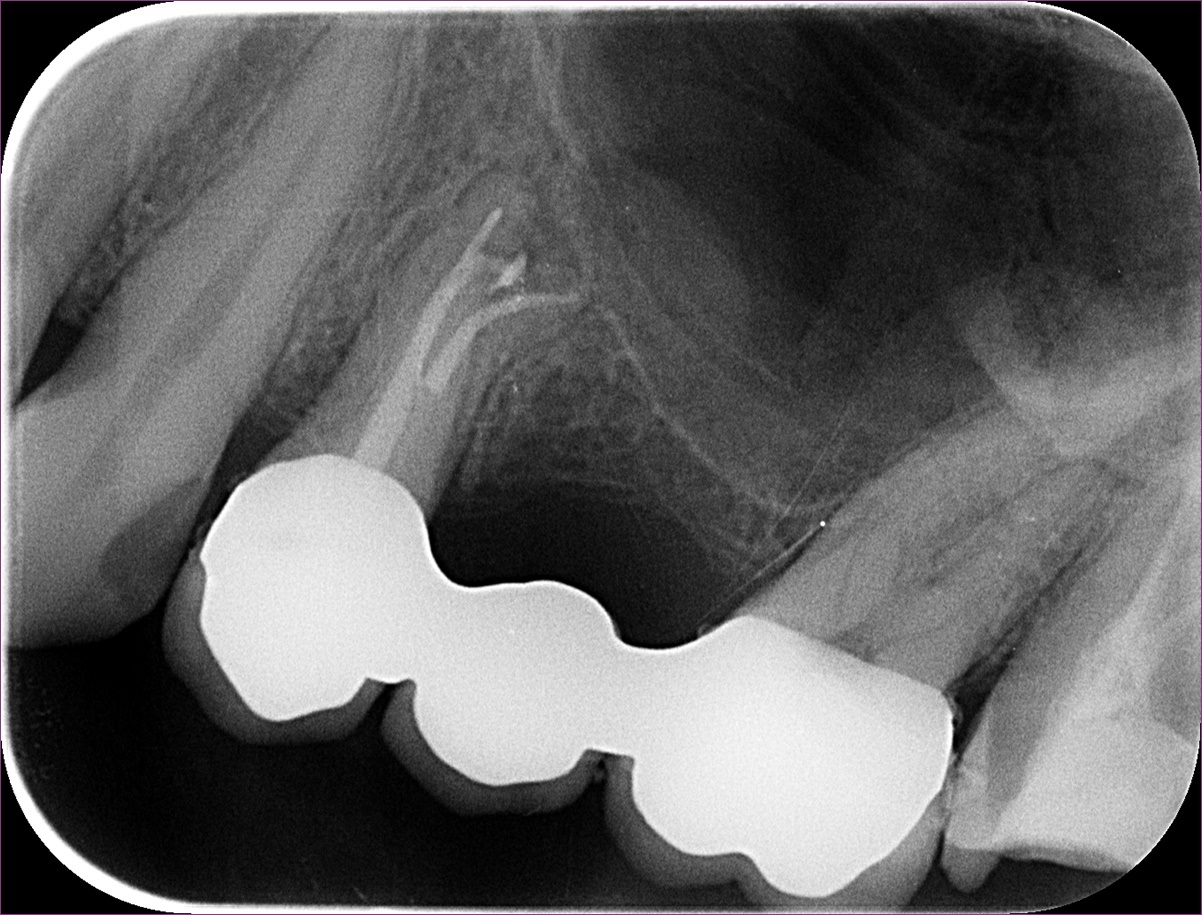

Mint minden alkalommal, a gyökértömés megkezdése előtt a fog csatornarendszerét többféle vegyszerrel, illetve egy speciális átöblítő rendszerrel kezeltük, hogy a benne lévő idegszövet-maradványokat teljes mértékben el tudjuk távolítani. Erre azért van szükség, mert az úgynevezett oldalcsatornákat mechanikusan, gyökérkezelő tűkkel nem tudjuk közvetlenül elérni. A gyökértömésről készült felvételen nagyszerűen látszik egy ilyen oldalcsatorna teljes feltelítődése: ezt nyilakkal jelöltük.